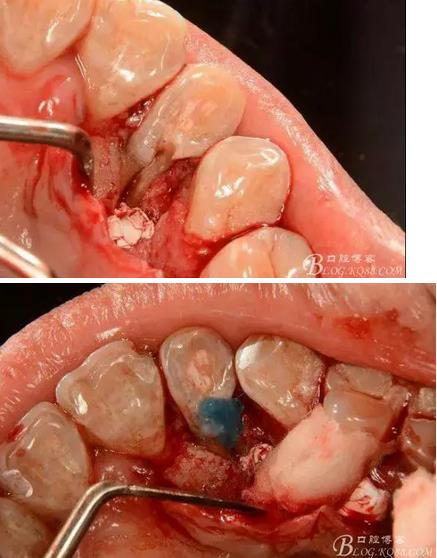

(1) 檢查:12唇側(cè)牙齦可見竇道,牙體顏色較鄰牙暗,無光澤,形態(tài)完整無缺損,唇側(cè)及近遠中向未提及牙周袋。腭側(cè)齦緣輕度紅腫,舌側(cè)窩可探及裂溝,可見浸墨狀痕跡,沿裂溝舌側(cè)探診牙周袋深大于11mm,除患牙外全口牙周狀況良好,為探及牙周袋,牙齦色粉紅。邊緣菲薄,質(zhì)地堅韌。12冷熱診無反應,叩診(+-),無明顯松動,無咬合創(chuàng)傷。12根尖x線片示,根管中三分之一中可見一斜向線樣透射影像根尖區(qū)及遠中根三分之一可見低密度透射暗影,錐形束CT示12根尖區(qū)唇腭向骨吸收已穿通,根面溝達根中三分之一卷曲分出另一牙根,再未見其他明顯的根管系統(tǒng)。

(3) 處理:常規(guī)開髓,修整髓腔,15#k銼探查根管,根管測量儀確定工作長度,根長22mm,大錐度手動銼完成根管預備,沒換一次銼沖洗根管一次,消毒,干燥根管,暫封維他派克斯。4%阿替卡因腎上腺素行11至14局部浸潤麻醉、消毒、鋪巾,做11-14腭側(cè)牙齦水平切口并翻瓣暴露12腭側(cè)骨缺損區(qū),清理肉芽組織及壞死骨組織,清潔術(shù)區(qū),磨除根面溝,制備固位溝槽,酸蝕,粘接,光固化樹脂修復根面缺損區(qū),阻斷牙周感染途徑。拋光樹脂,沖洗創(chuàng)面,復位齦瓣,局部敷料壓迫一分鐘,對位縫合齦瓣。術(shù)后抗炎治療,7d線。